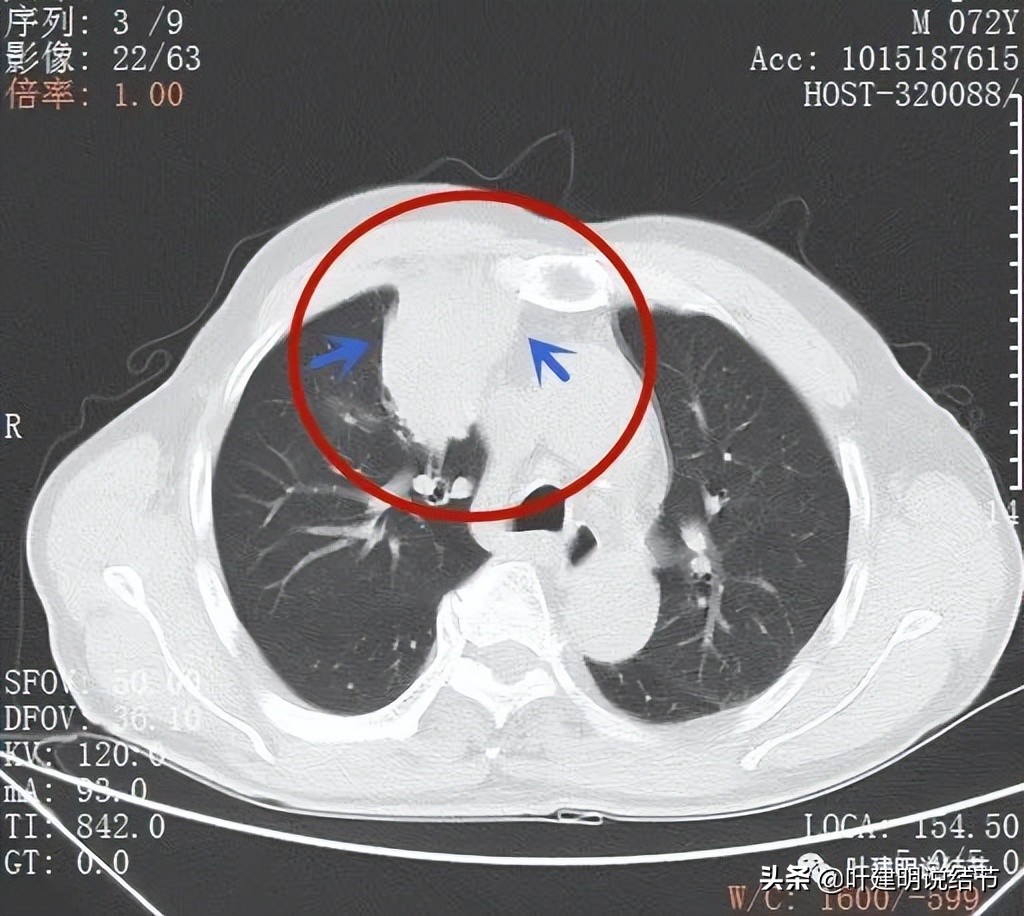

支气管似乎没有明显被侵犯或压迫(黄色箭头),边缘平滑(蓝色箭头)

上叶前段支气管(黄色箭头),病灶边缘缺乏膨胀性(蓝色箭头)